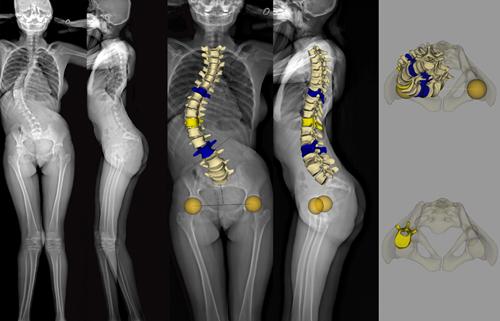

The EOS imaging system provides full-body images of patients in a natural standing or seated position, both in 2-D and 3-D. It automatically calculates a broad range of clinical parameters essential to diagnosis and surgical planning, allowing for more informed diagnosis and treatment of orthopedic conditions, including scoliosis, degenerative spine conditions and lower limb joint conditions. Notably, EOS offers high-quality images while delivering a radiation dose that is nine times lower than that of computed radiography X-ray and 20 times lower than basic computed tomography (CT) scans.